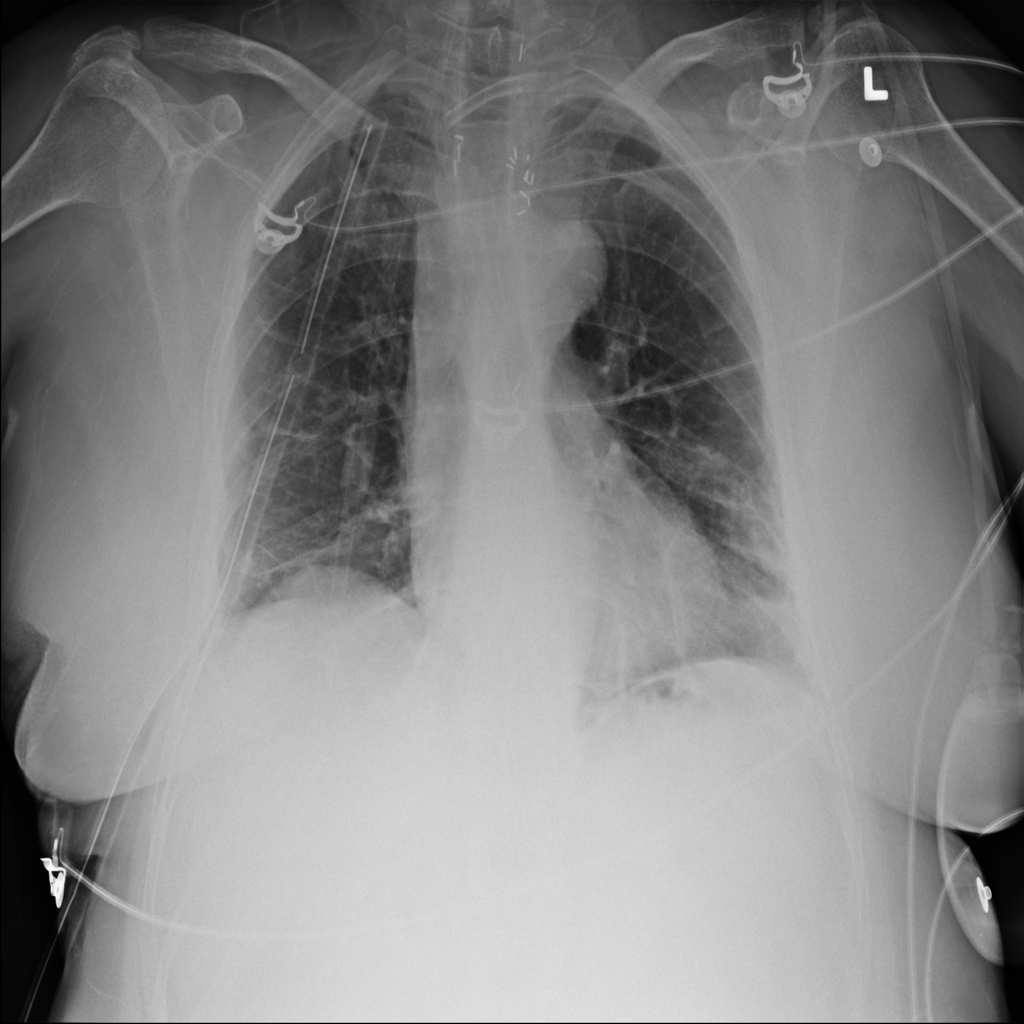

PAT-3384 · IMG-054Atelectasis

PAT-3384 · IMG-054

AP